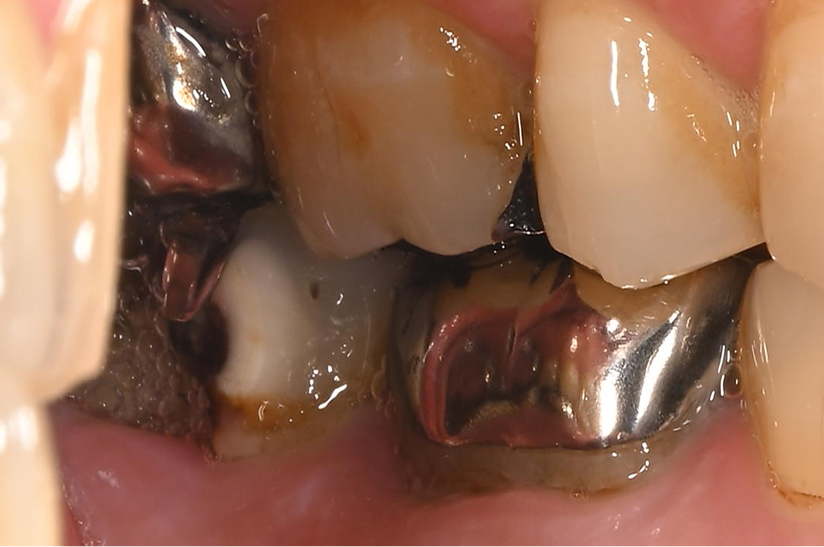

大臼歯の再根管治療を行った症例

タップで写真の拡大ができます。

Before&After(根管治療)

Before

主訴

歯茎が腫れて、噛むと違和感がある

治療内容

再根管治療(大臼歯)

治療期間

1ヶ月

治療費用

165,000

治療の

リスク

処置中に歯肉縁下におよぶ重度のう蝕や破折を認めた場合、治療を中断する可能性があります。術後も症状が残る場合は追加の処置が必要になる可能性があります。